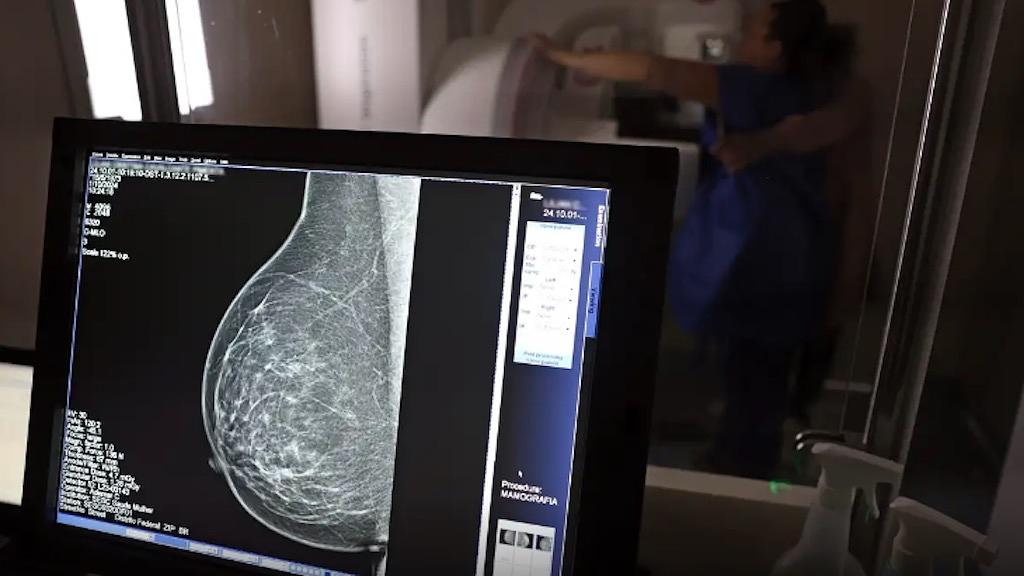

No mesmo local, a dona de casa Lilian Cristina Cavalcanti, fez pela primeira vez uma mamografia, a radiografia específica das duas mamas que possibilita a identificação precoce de alterações nos seios. Com 51 anos e mãe de três filhos, ela admite que, até hoje, deixou a questão de lado por falta de tempo e por achar que seria difícil conseguir a vaga em uma unidade pública de saúde. “Nunca tentei. Não tenho paciência para ficar na fila esperando e, como nunca senti nada (no autoexame da mama), deixei passar”, confessou.

Mas, chegou a hora dela realizar a mamografia bilateral. Lilian Cristina se posicionou em pé, em frente ao aparelho e, imóvel, teve as mamas comprimidas em diferentes ângulos para captura das imagens detalhadas. No fim, ela saiu da carreta do Sesc com impressões positivas sobre o exame. “Achei que doía mais, mas foi bem tranquilo. Agora, espero ansiosa pelo resultado do exame.”

André Abreu, do Sesc-DF, explica que as imagens em alta resolução captadas pelos mamógrafos são enviadas automaticamente aos profissionais do Hospital de Barretos (SP) para análise e emissão do laudo médico, em até 30 dias. “Se o laudador já identificar visualmente um câncer, ele avisará a equipe de Brasília que poderá ter que repetir o exame e esta deverá encaminhar a mulher examinada como paciente ao Hospital de Base de Brasília”. Nos demais casos, quando for constatada a normalidade das mamas, a mulher receberá o laudo em um envelope nominal no prazo citado, no mesmo local, a rodoviária do Plano Piloto.

O técnico em radiologia Ademar Cardoso revelou que, nos dez anos de atuação na área, muitas vezes percebeu a presença de nódulos nas mamas de pacientes ainda no momento de realização da mamografia e comenta a relevância da prevenção. “Muitas vezes vejo pessoas sem informação e, por isso, o exame de graça é tão importante, porque é feito o encaminhamento necessário e a paciente pode dar início a tratamento, quando for o caso.”